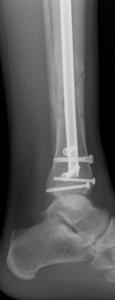

Tibia shaft fractures in adults can be treated by a variety of techniques depending on many factors. Some of these techniques might even be used in combination at times and include: casting, bracing, external fixation (where pins are inserted into the bone and connected to rods outside of the skin), plates and screws, and rods (also referred to as nails) placed inside the bone (Figure 1). The time it takes for a tibia shaft fracture to heal can vary greatly depending on the characteristics of the injury as well as patient factors. One of the most important modifiable patient factors that can delay healing in tibia fractures is tobacco/nicotine use. Nicotine use can significantly inhibit bone healing and a tibial shaft fracture is an excellent reason to stop smoking.

Fig 1. Tibia fracture treated with a rod and screws